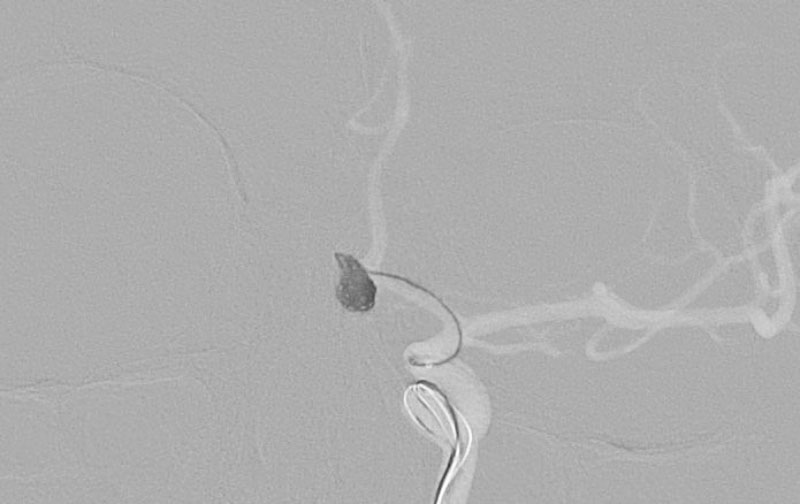

くも膜下出血

左中大脳動脈瘤破裂

40代

救急外来

No.1596 手術前

No.1596 手術中

No.1596 手術後